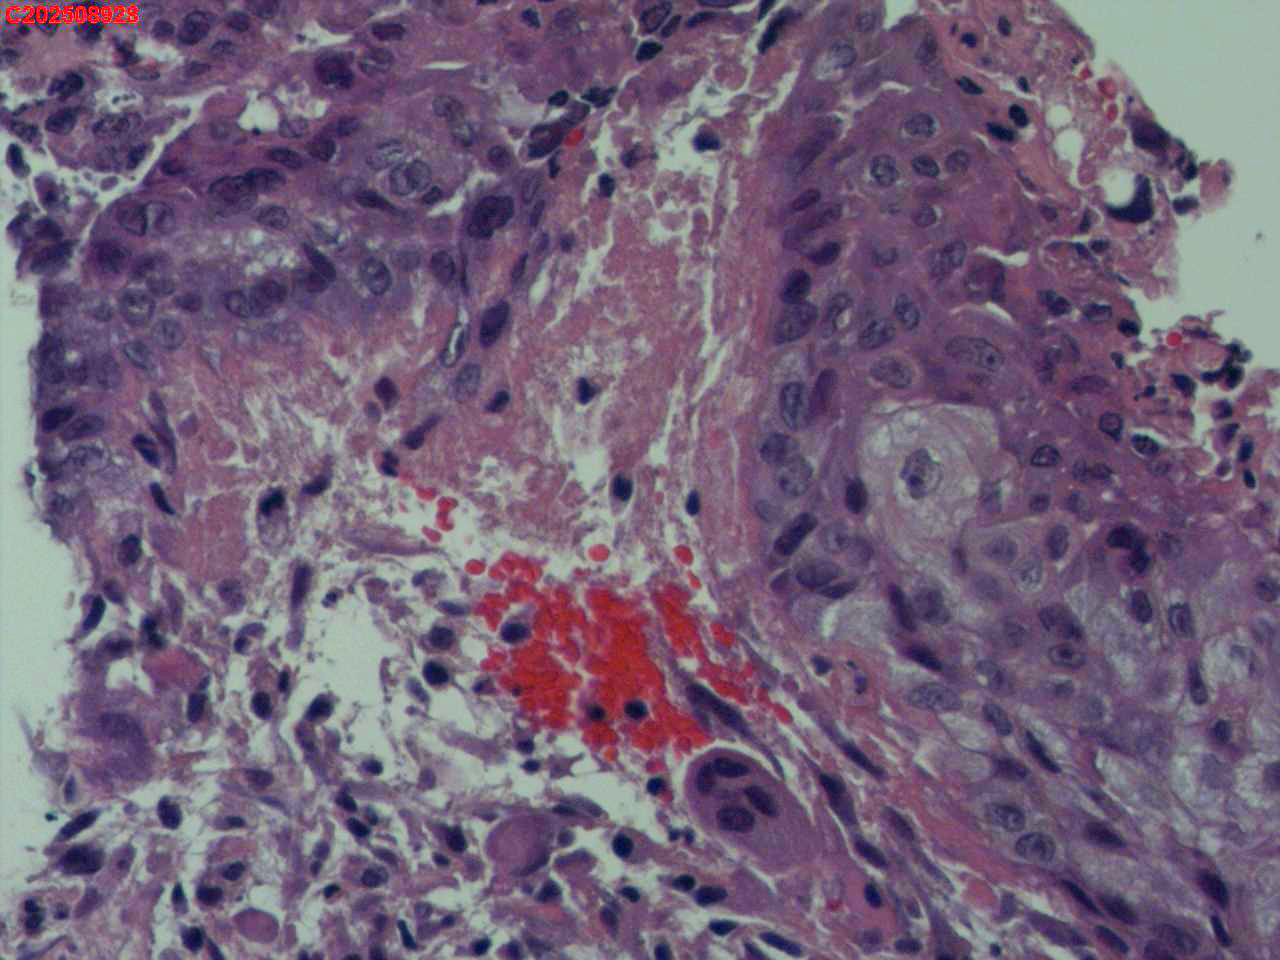

喉部右侧、声带下方咬检

男

56岁

喉Ca?

咳嗽

喉室内右侧声带下方新生物。

考虑鳞癌

鳞癌,有微浸润